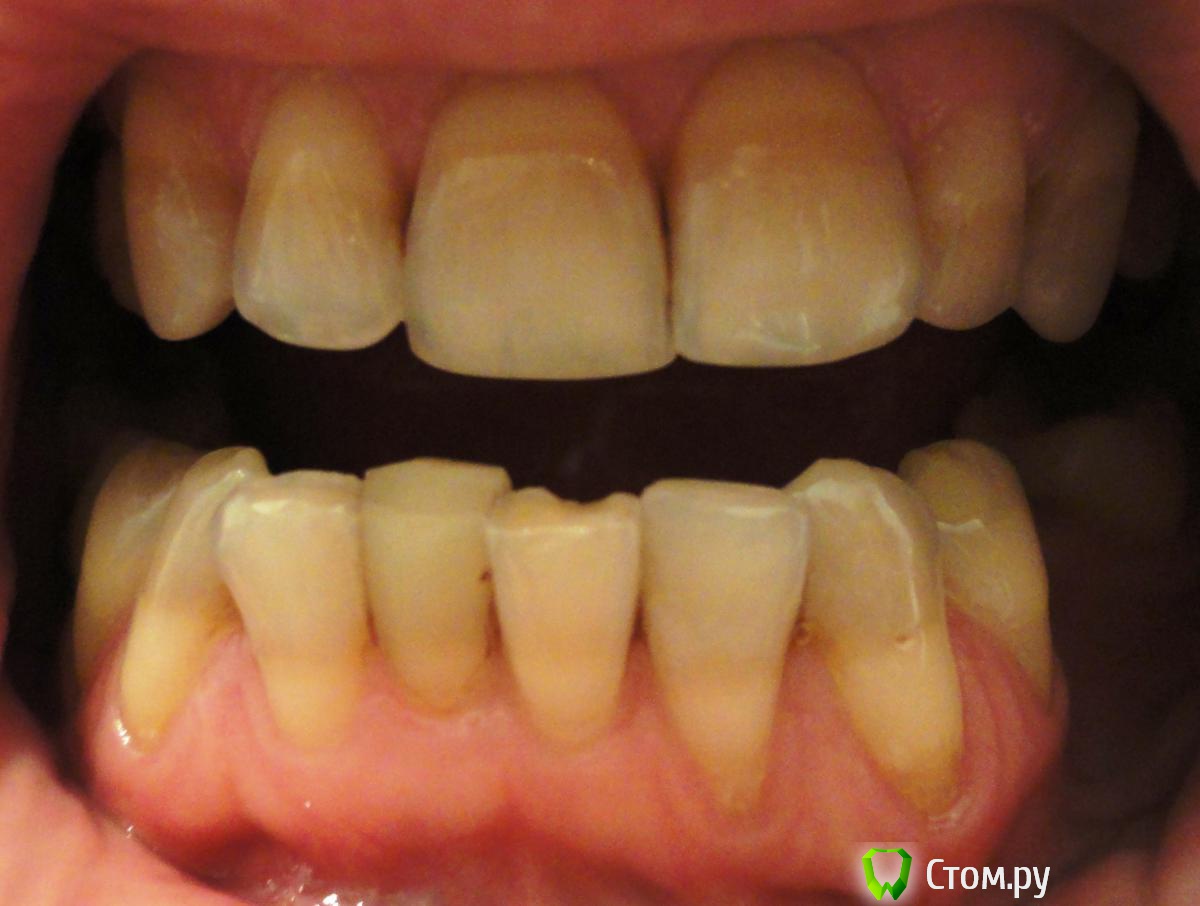

Необыкновенная Опубликовано 17 октября, 2014 Поделиться Опубликовано 17 октября, 2014 (изменено) Добрый день, уважаемые стоматологи!Прошу совета:Фото № 1 - рецессия десны на нижних зубах. Вопрос - что можно сделать? Что, в 2-х словах, представляет из себя методика / (операция) / варианты? Какова гарантия приживаемости? Надолго ли хватает? Фото № 2 - из-за той же рецессии и клиновидных дефектов, появилось оголение корней (конкретные на фото 4, 5, 6 - пойдут под коронки). У 6-ки корень красный (резорциновый вроде говорили?). Вопрос - т.к. после установки коронок будут видны корни из-за ушедшей десны, ВОЗМОЖНО ЛИ хирургически воссоздать нормальный десневой край и сосочки? Розовую керамическую десну не хочу ((Фото № 3 - ОПТГ - прилагаю на всякий случай, по кости вроде пока всё в норме. Или уже нет?(просьба не пугаться глубокой коричневой полосы на зубах, я не курю и посещаю гигиениста иногда )) - это тетрациклин, отбеливание не помогает (и больно). И просьба не пугаться скученности, ортодонтическое лечение было давно (всё вернулось), готовлюсь к протезированию. Спасибо всем заранее за рассмотрение вопроса и консультации!!! Изменено 17 октября, 2014 пользователем Необыкновенная Ссылка на комментарий

SDC Опубликовано 17 октября, 2014 Поделиться Опубликовано 17 октября, 2014 (изменено) Добрый день, уважаемые стоматологи!Прошу совета:Фото № 1 - рецессия десны на нижних зубах. Вопрос - что можно сделать? Что, в 2-х словах, представляет из себя методика / (операция) / варианты? Какова гарантия приживаемости? Надолго ли хватает? Фото № 2 - из-за той же рецессии и клиновидных дефектов, появилось оголение корней (конкретные на фото 4, 5, 6 - пойдут под коронки). У 6-ки корень красный (резорциновый вроде говорили?). Вопрос - т.к. после установки коронок будут видны корни из-за ушедшей десны, ВОЗМОЖНО ЛИ хирургически воссоздать нормальный десневой край и сосочки? Розовую керамическую десну не хочу ((Фото № 3 - ОПТГ - прилагаю на всякий случай, по кости вроде пока всё в норме. Или уже нет?(просьба не пугаться глубокой коричневой полосы на зубах, я не курю и посещаю гигиениста иногда )) - это тетрациклин, отбеливание не помогает (и больно). И просьба не пугаться скученности, ортодонтическое лечение было давно (всё вернулось), готовлюсь к протезированию. Спасибо всем заранее за рассмотрение вопроса и консультации!!!Фото № 1 Возможно закрыть множественные рецессии десны, желательно ортодонтическое лечение. В 2-х словах :подтяжка десны с утолщением биотипа за счет трансплантации слизисто-десневого трансплантата с неба. Хватает надолго. Гарантия - это означает, что доктор или клиника берет на себя обязательства по устранению осложнений и/или проведение повторной операции без доп. оплаты. Гарантировать реакцию Вашего организма доктор не может. Фото №2 нет необходимости в закрытии рецессии. Просто коронки на 4, 5, 6-й зубы. Межзубные сосочки в норме. Обнажение корней на 6-м зубе произошло за счет его выдвижения в сторону дефекта з. ряда на н.ч. На 4-м - дефект твердых тканей в пришеечной области скорее всего из-за перегрузки Фото № 3 С костной тканью в области зубов относительный порядок, есть необходимость в восстановлении непрерывности зубных рядов с применением имплантации. Изменено 17 октября, 2014 пользователем SDC Ссылка на комментарий